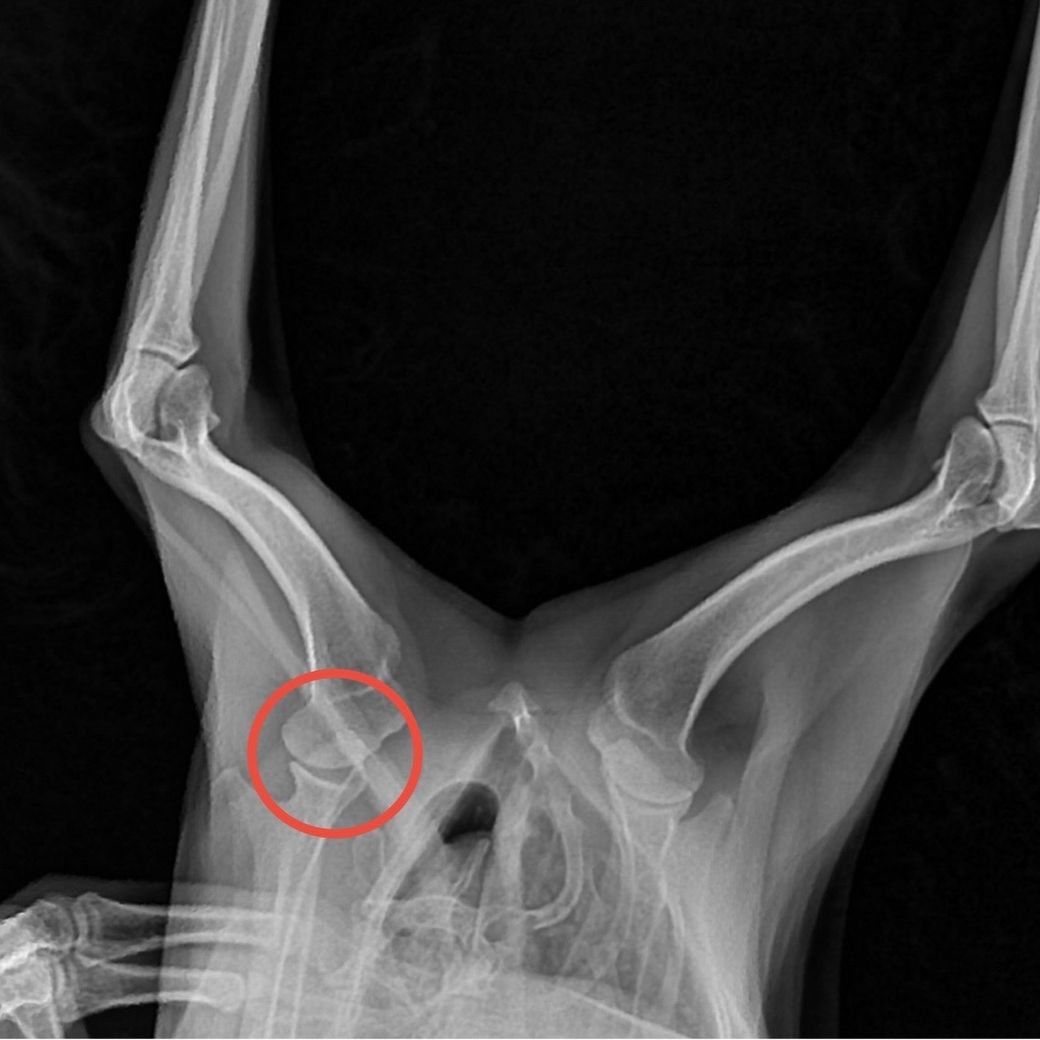

강아지 나이가 올해 12살로 노견에 접한지 오래 됐는데요. 평소 산책을 하면 한시간은 기본으로하고 아직 팔팔하다고 느낄 정도로 잘 뛰어다녔는데, 갑바기 며칠동안 깨갱 거리고 앞 다리를 잘 못딛기에 병원에 갔더니 어깨쪽 인대가 늘어났다고 하더라고요. 지금은 약 먹고 아파하는게 줄어들긴 했지만 앞으로 관리를 어떻게 하는게 좋을지 궁금합니다.

• 안녕하세요. 박창민 수의사입니다. 보존적 관리 방법이 있습니다. 일단 지금부터 짧게는 4주 길면 8주까지 안정 및 활동 제한을 해주시는 게 좋고 체중 관리, 물리 치료, 통증 관리를 병행해주셔야 합니다. 감사합니다.

반려견의 최소 산책 횟수 기준인 매일 아침저녁 하루 2회 이상 각 10분 이상의 산책을 잘 챙겨주시고, 짧고 잦은 빈도의 산책을 중심으로 운동 요법을 하시기 바랍니다.